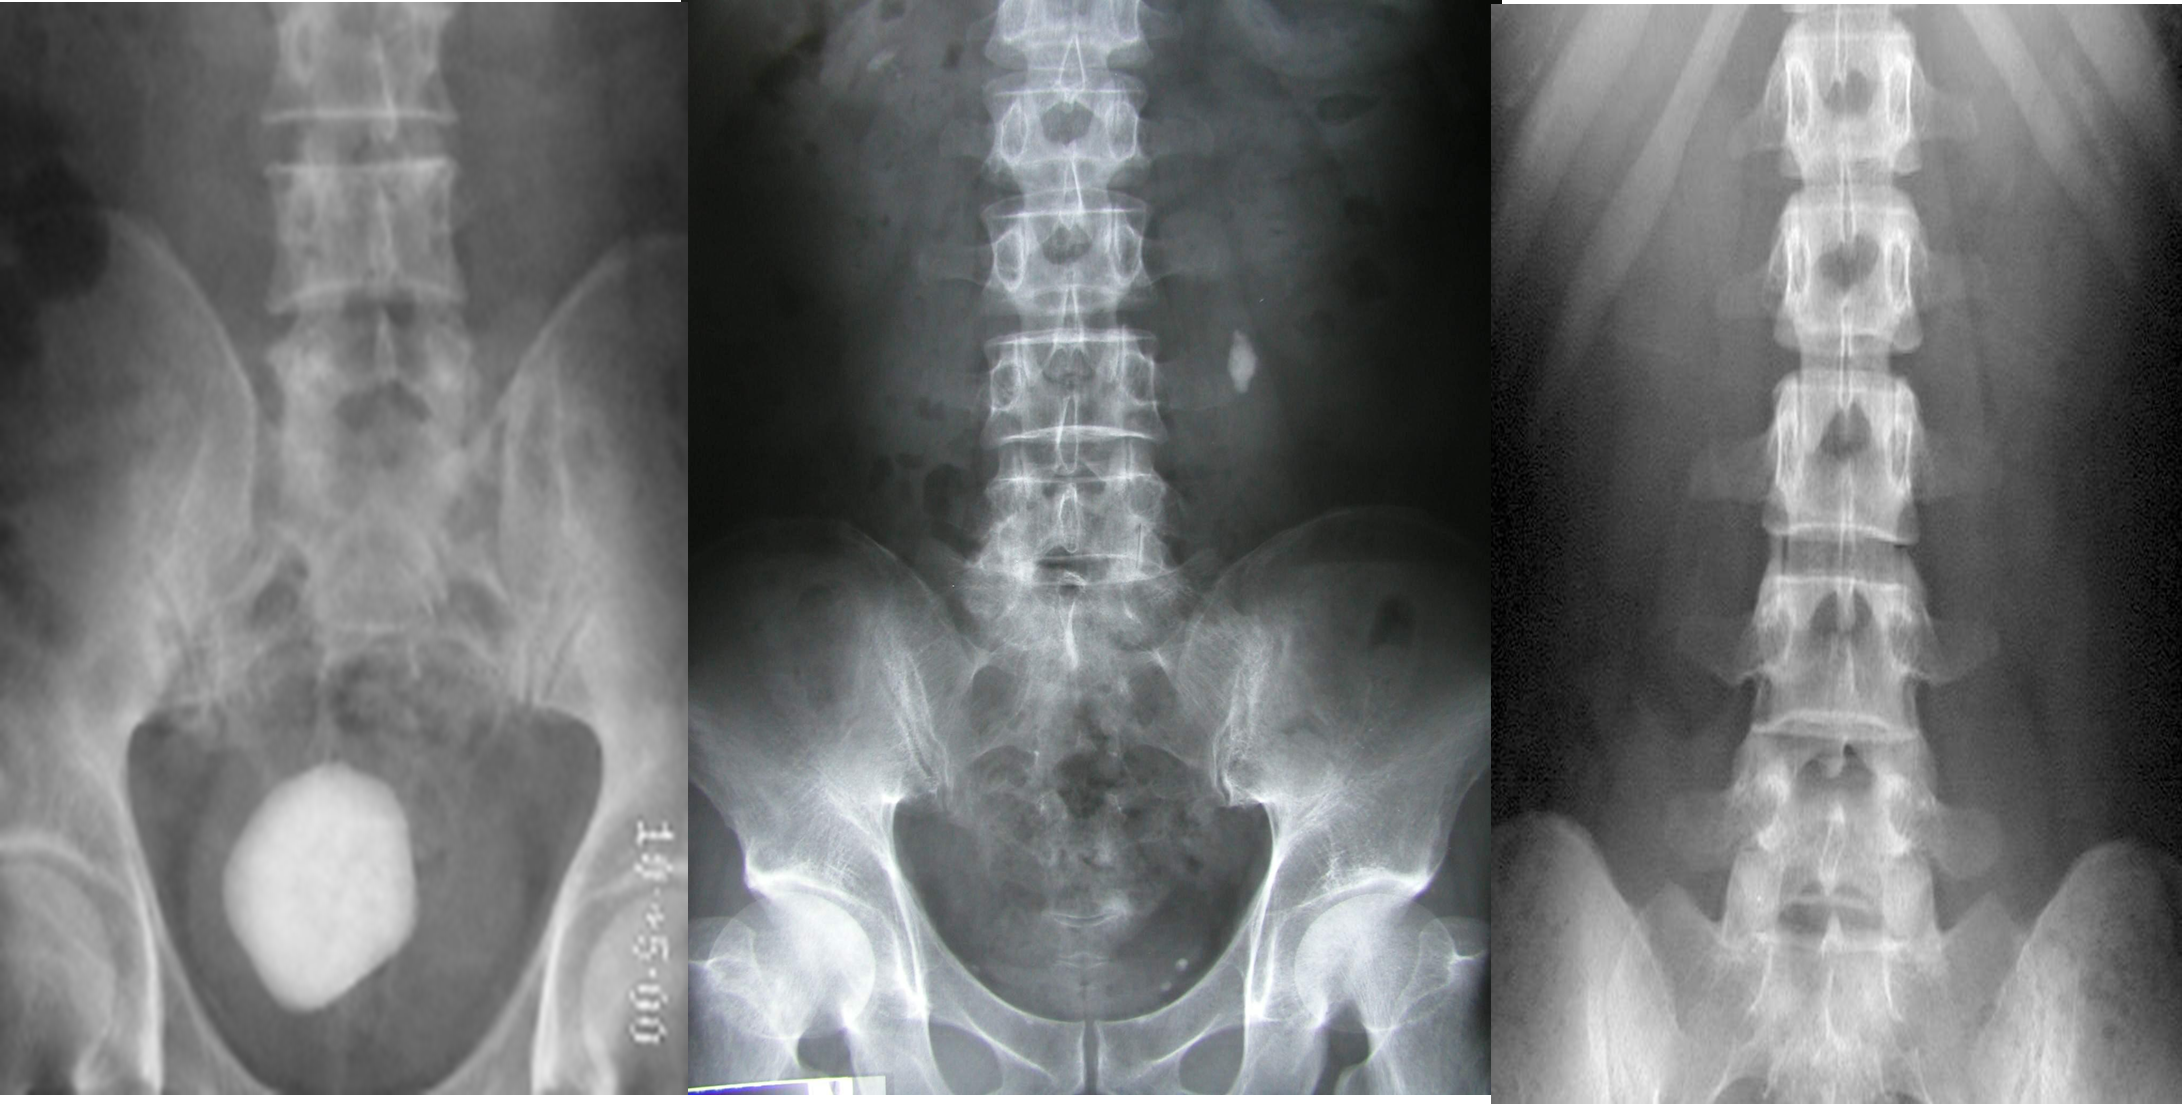

PLAIN X-RAY

KUB

Good for evaluation of radiopaque stones

Because KUB sensitivity is proportional to stone size, it is usually only suitable for larger stones.

1- Radio-opaque stone